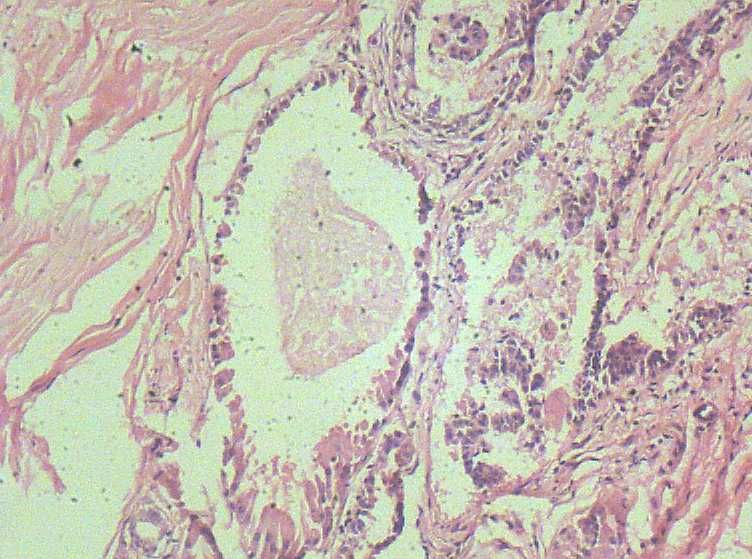

B3774乳腺积乳性包块?

女41岁,左腺包块。肉眼:不整形囊壁样组织,大小2*1.6*0.3CM,壁厚0.1—0.3,未触及结节,未见出血及坏死。

标签:乳腺纤维囊性增生症

似乎有导管扩张、慢性炎细胞浸润、大汗腺化生、普通型导管增生等病变,没有看到囊壁内衬上皮或囊壁结构。